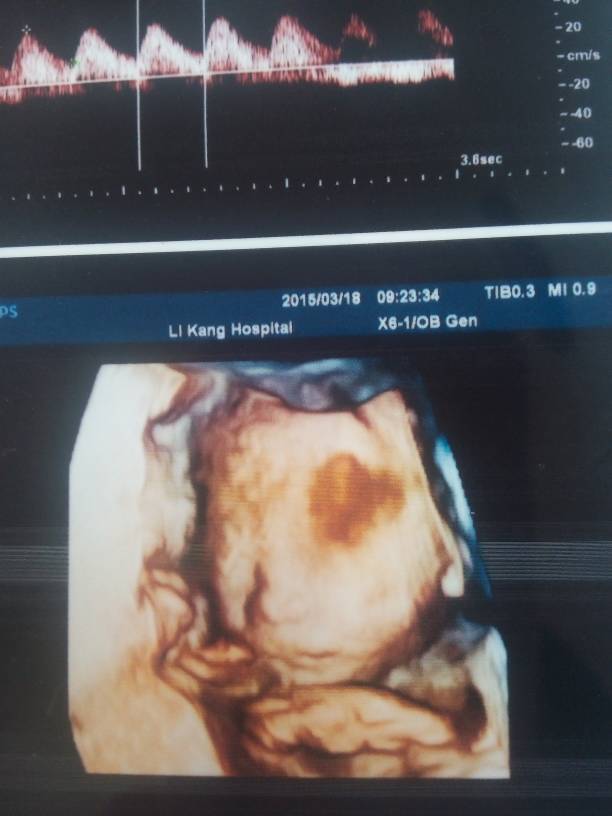

25周做的四维,眼睛那有黑影,医生说应该没啥事,说是胎盘挡的,可还是担心,宝妈有没有这种情况的 25周做的四维,眼睛那有黑影,医生说应该没啥事,说是胎盘挡的,可还是担心,宝妈有没有这种情况的 点击展开 150*****444_Aqjs 2015-03-25 13:32 为您推荐: 其他回答 相信医生的。 泛泛。 2015-03-25 14:59 有没有让你去复查呀 难过又怎样我还有影子 2015-03-25 13:58 你可以再去复查看看 保定亿家馨家政月嫂育婴师 2015-03-25 13:44 都是这样,没事的 俊宝宝150501 2015-03-25 13:40 以后再做做看看如果不放心的话! 我爱我家三宝 2015-03-25 13:37 加载更多 相关问题 做了四维彩超,医生说胎盘有点低,到不要紧,请问各位宝妈,有同样情况的嘛,都怎么做的 为什么我做四维医生没有跟我说我的胎盘成熟度呢? 22周时四维胎盘0级,医生说要加强营养 22周胎盘0级算正常吗?